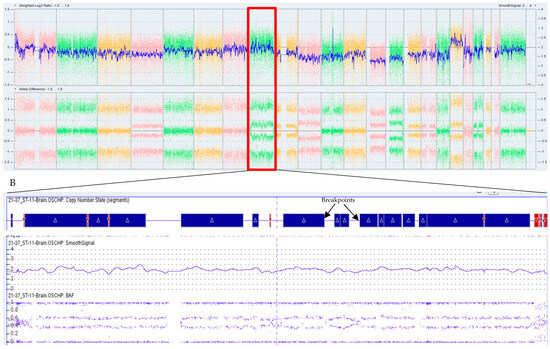

3.3. OGM Clearly Defined an SV Event

3.4. OGM Detected the Cryptic SV Events

3.4.1. A Complex Translocation Event

3.4.2. Three-Way Translocation Event